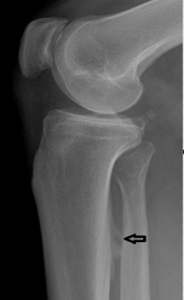

3. Prominent Soleal Line

Figure 4 demonstrates prominent ossification that obliquely traverses the proximal tibia at the origin of the soleus muscle. Figure 5 demonstrates a thick osseous protrusion along the posterior tibia. This normal variant can be mistaken for an aggressive periosteal reaction or pathologic heterotopic ossification. But the anatomic orientation of the ossification along the soleal insertion and no involvment of the underlying bone should allow the clinician to easily identify this variant. This normal viariant has also been termed tibial pseudoperiostitis or tibial tug lesion.